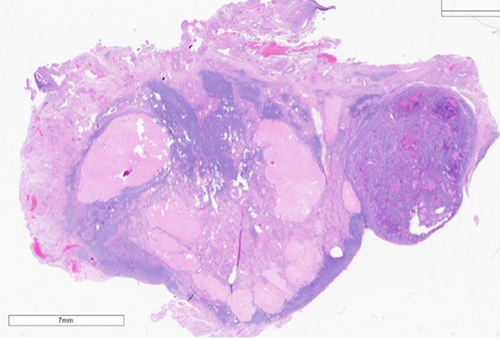

A female patient in her 70s presented to her gynecologist complaining of intermittent lower abdominal pain, bulk symptoms, cramping, and vaginal spotting for 6 months. Her medical history is significant for breast cancer diagnosed over 10 years ago and class II obesity. The patient underwent a pelvic ultrasound which revealed an 8 mm endometrial stripe and a 7 cm x 5 cm left uterine mass [figure 1] deemed a uterine fibroid. Endometrial biopsy showed carcinosarcoma and the patient subsequently underwent hysterectomy and bilateral salpingo-oophorectomy. The tumor measured 11.5 x 10.0 x 3.1 cm and was semi-firm, tan-white, friable, and exophytic on gross examination. F myometrial invasion into the serosa and involvement of bilateral ovaries and fallopian tubes was identified. [figure 2]

Figure 3. Medium power view of high-grade malignant stroma surrounding malignant high-grade glandular epithelium arranged in a biphasic pattern.

The stromal component above reflects a homologous undifferentiated sarcoma composed of polymorphous round to spindled cells with large vesicular nuclei, coarse chromatin, scant cytoplasm, and readily identifiable mitotic figures. The epithelial component above demonstrates serous carcinoma, however, can be composed of endometrioid, clear cell, or squamous carcinoma.